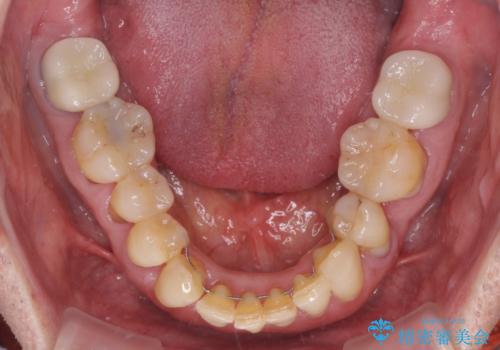

上の歯は見た目を良くしたいというご希望があったため、歯周外科処置を行った歯についてはセラミッククラウンで補綴することとしました。

患者様ご自身が痛みには強いとおっしゃっていたので、治療中は特に辛いと感じることはなく進めることができました。

気になっていた歯の痛みや歯肉からの出血がなくなり、改善したいと思っていた外見も綺麗に仕上がり、大変満足していただきました。